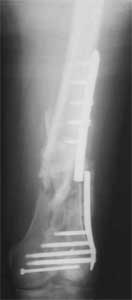

A new toy is more interesting and fashionable. And anyway it is not panacea, i have already seen presentations with LISS failures like the attached one presented by D.Seligson. And people also demonstrated incisions say that the method is not so LESS invasive as it supposed to be.